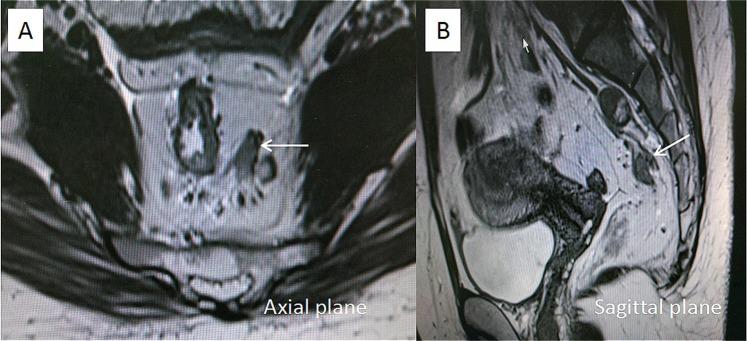

The purpose of this study was to evaluate the prognostic significance of the magnetic resonance imaging-detected extramural venous invasion (MR-EMVI), the depth of mesorectal extension (MR-DME), and lymph node status (MR-LN) in clinical T3 mid-low rectal cancer. One hundred and forty-six patients with clinical T3 mid-low rectal cancer underwent curative surgery were identified. Pretreatment high-resolution MRI was independently reviewed by two experienced radiologists to evaluate MR-EMVI score (0-4), MR-DME (≤4 mm or >4 mm), and MR-LN (positive or negative). The Cox-multivariate regression analysis revealed that the MR-EMVI was the only independent prognostic factor that correlated with overall 3-year disease-free survival (DFS) (p = 0.01). The survival analysis showed that patients with positive MR-EMVI, MR-DME > 4 mm, and positive MR-LN had a poorer prognosis in the overall 3-year DFS (HR 3.557, 95% CI 2.028 to 13.32, p < 0.01; HR 3.744, 95% CI:1.165 to 5.992, p = 0.002; HR 2.946, 95% CI: 1.386 to 6.699, p < 0.01). By combining MR-EMVI with MR-DME or MR-LN, the prognostic significance was more remarkable. Our study suggested that the MR-EMVI, MR-DME, and MR-LN were the important prognostic factors for patients with clinical T3 mid-low rectal cancer and the MR-EMVI was an independent prognostic factor.

本研究旨在评估磁共振成像检测到的外膜静脉侵犯(MR-EMVI)、直肠系膜延伸深度(MR-DME)和淋巴结状态(MR-LN)在临床 T3 中低位直肠癌中的预后意义。我们确定了 146 例接受根治性手术的临床 T3 中低位直肠癌患者。两名经验丰富的放射科医生对术前高分辨率 MRI 进行独立评估,以评估 MR-EMVI 评分(0-4 分)、MR-DME(≤4mm 或>4mm)和 MR-LN(阳性或阴性)。Cox 多因素回归分析显示,MR-EMVI 是唯一与总 3 年无病生存率(DFS)相关的独立预后因素(p=0.01)。生存分析显示,MR-EMVI 阳性、MR-DME>4mm 和 MR-LN 阳性的患者总 3 年 DFS 预后较差(HR 3.557,95%CI 2.028-13.32,p<0.01;HR 3.744,95%CI:1.165-5.992,p=0.002;HR 2.946,95%CI:1.386-6.699,p<0.01)。通过将 MR-EMVI 与 MR-DME 或 MR-LN 相结合,预后意义更加显著。我们的研究表明,MR-EMVI、MR-DME 和 MR-LN 是临床 T3 中低位直肠癌患者的重要预后因素,MR-EMVI 是独立的预后因素。